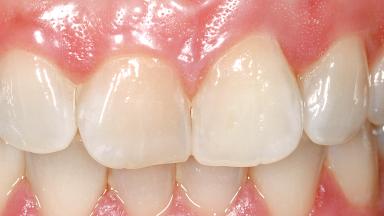

Immediate Flapless Placement of an Implant in a Maxillary Left Central Incisor Site

A 29-year-old female patient presented for treatment to replace the upper left central incisor tooth with an implant- supported restoration. The tooth had been intermittently symptomatic for the previous 12 months. The tooth had originally suffered trauma about 15 years previously. Several endodontic treatments had been performed, including an apicectomy procedure to retain the tooth. The patient was healthy and a non-smoker. She had reasonable expectations in regard to esthetic outcomes and the risk of marginal tissue recession following treatment. At medium smile, the gingival margins of the upper teeth were visible, with a display of 3 to 4 mm of the gingival margins. Gingival recession of tooth 21 and a discrepancy in the gingival levels between teeth 11 and 21 was observable during normal speech and smile.

Patient's Esthetic Expectations Low Medium High

Lip Line No exposure of papillae Exposure of papillae Full exposure of mucosa margin

Periodontal Phenotype Low-scalloped, thick Medium-scalloped, medium-thick High-scalloped, thin